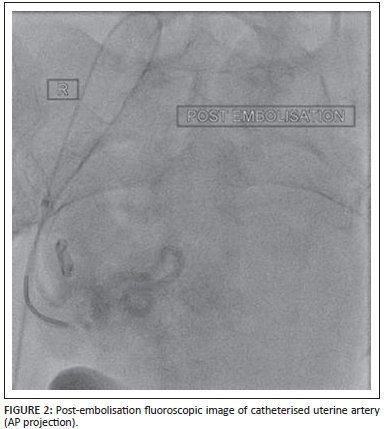

All uterine artery embolisations were performed in the interventional radiology suite at Steve Biko Academic Hospital. Patients were given either spinal or general anaesthesia at the discretion of the attending anaesthetist as per the protocol of the Department of Anaesthesia. Right common femoral arterial puncture was performed, followed by arteriography of the pelvic vessels. The uterine arteries were sequentially catheterised using a Roberts catheter (Cook Inc., Bloomington, Indiana, USA). The embolic agents in all cases were a combination of non-absorbable polyvinyl alcohol particles (300μm - 500m) and gelfoam. In all procedures, both uterine arteries were successfully embolised (Figure 1, Figure 2). Post-embolisation anaesthesia was provided at the discretion of the anaesthetist as a combination of opioids and benzodiazepines.